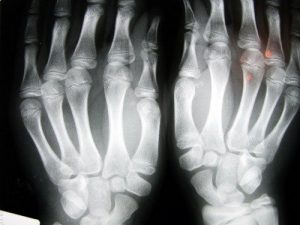

ऑस्टियोपोरोसिस हड्डियों का एक रोग है जो बोन मास या हड्डियों का घनत्व कम कर देता है। इस रोग का लक्षण है छेददार हड्डियाँ। अंदरूनी कोशिकाओं का आकार बढ़ाकर हड़्डियाँ भुरभुरी हो जाती हैं और ज्यादा आसानी से टूट जाती हैं।

कलाई में और हिप के वर्टिब्रा में भी बार-बार फ्रैक्चर होते हैं। यह सबसे गंभीर फ्रैक्चर है क्योंकि इसे तुरंत सर्जिकल इंटरवेंशन की जरूरत है। रोगी के स्वास्थ्य पर भी इसका गंभीर परिणाम होता है।